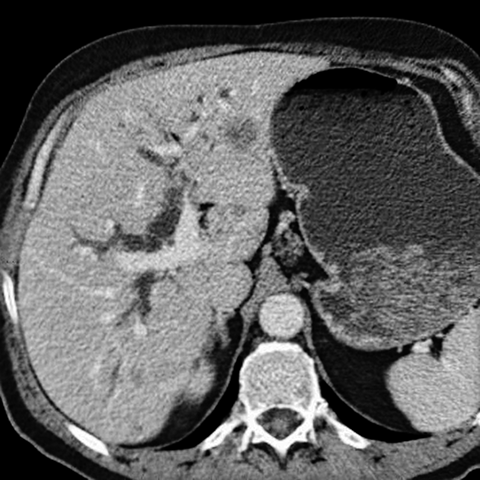

56 year-old male with painless jaundice [2 of 4]]